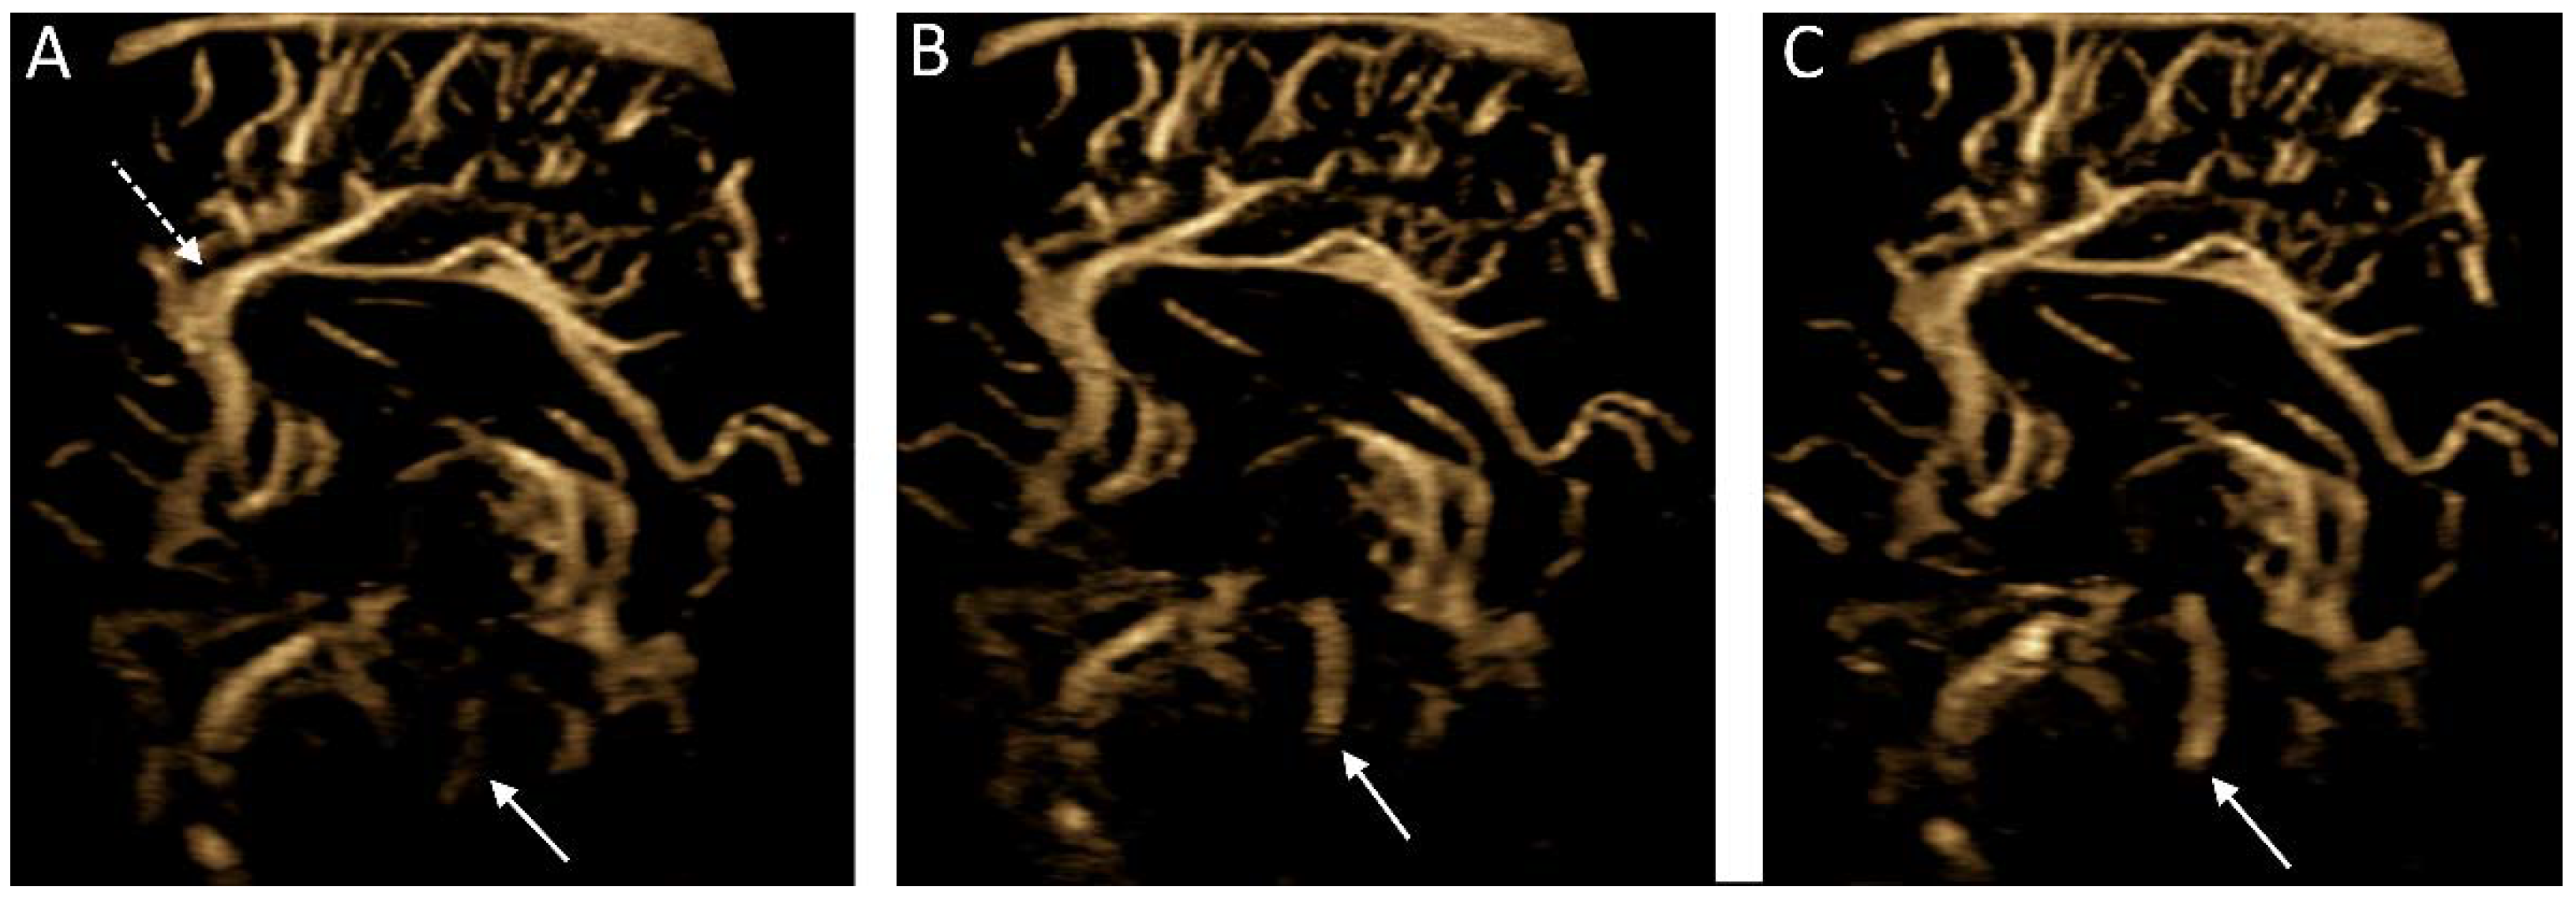

Figure 7.

Microvascular imaging of the brain acquired in a in a midsagittal plane. (A–C) Consecutive images were acquired demonstrating cerebrospinal fluid flow within the cerebral aqueduct (solid arrows). Note is made of the anterior cerebral artery and its branches (dashed arrow).